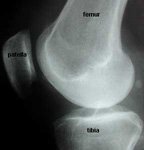

On this X-ray the red line marks what is referred to as Blumensaat's line.

Blumensaat's line in patella alta

Blumensaat's line is also useful in the diagnosis of patella alta, or high-riding patella.

Extending the line to beyond the X-ray shadow of the patella (kneecap) gives an indication of whether or not the patella is abnormally high or low, as it would normally intersect the lower pole of the patella.

Note the relationship of the patella to Blumensaat's line. Peer-reviewed papers Quote from peer-reviewed paper:

"....Blumensaats line should extend to the inferior pole of the patella at 30 degrees of knee flexion...."